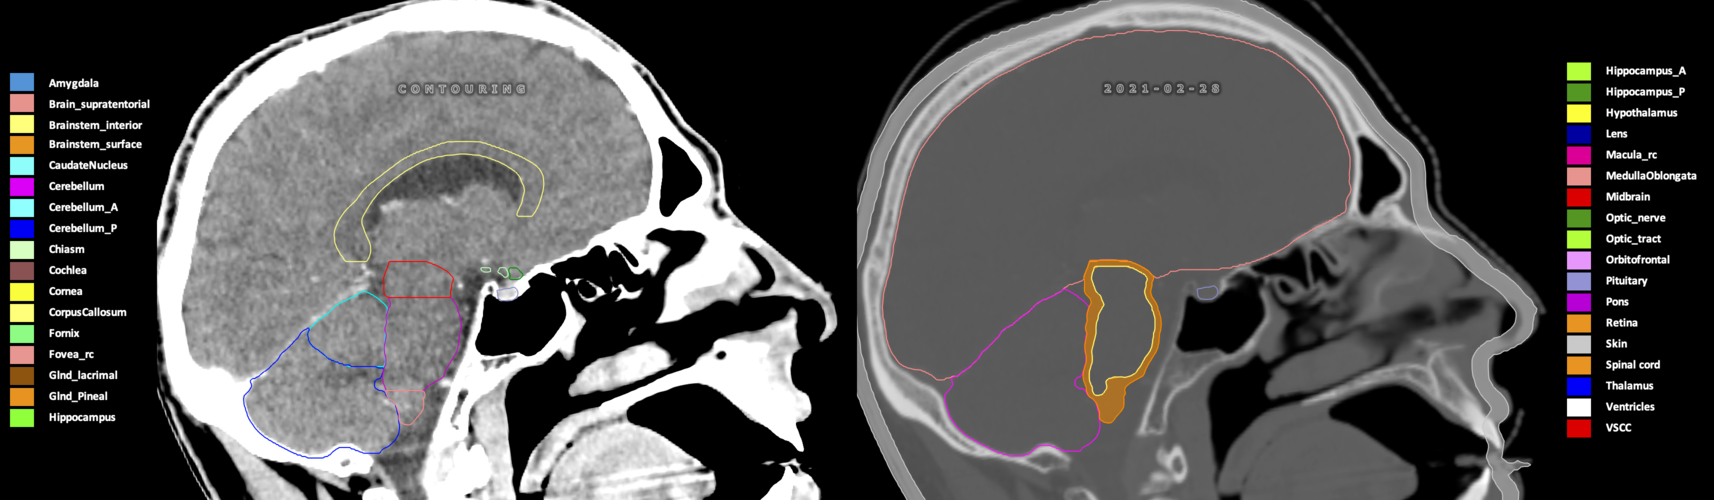

Included are all OARs known to be relevant for radiation-induced toxicity in neuro-oncology: brain, brainstem (midbrain, pons, medulla oblongata), chiasm, cerebellum (anterior & posterior), cochlea, cornea, hippocampus (anterior & posterior), hypothalamus, lens, lacrimal gland, optic nerve, pituitary, skin, and vestibular & semicircular canals. To further facilitate research on cognition, vision and radiological changes after irradiation of the brain, potential clinically-relevant OARs are included: amygdala, caudate nucleus, cerebellum (anterior & posterior), corpus callosum, fornix, macula, optic tract, orbitofrontal cortex, periventricular space (PVS), pineal gland, and thalamus.

Three-dimensional delineation of the 25 consensus OARs for neuro-oncology are shown on CT (WW/WL 120/40, 3000/600), 3T MR images, (T1Gd, T2FLAIR 1mm) and 7T MR (MP2RAGE 0.7 mm). All are presented in transversal, sagittal and coronal view.